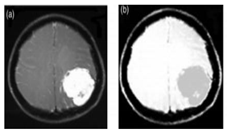

2.2. Segmentation of Brain Regions

2.2.1. Related-Work to the Segmentation of Brain Regions